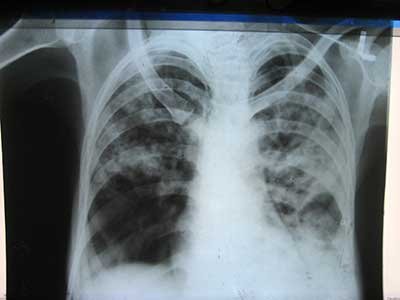

The Tuberculosis or TB and Leprosy Focal person attached to the District Health Management Team Kono Samuel Mills, has said that the district is presently at 92.1 % treatment success rate of Tuberculosis or T.B.

According to Mr. Mills, the objective of the District stakeholders sensitization session was for the participants to know what is Tuberculosis, it’s preventive and creative measures including plans put afoot to maintain the impacts so far achieved in the fight against the disease in the district and Country as whole. He said Kono District since started admitting multi- drug resistance patients and therefore appealed to all and sundry to be tested in order to know their status as prevention is cheaper and better than cure.

Samuel Mills intimated the audience that in the not too distant future, his department with support from the Ministry of Health and Sanitation including its partners, would soon create TB treatment centers at the different correctional centers across the country. He thanked the community Health Workers for being hard working and very committed to work. He urged them not to relent because they are the secret behind the 92.1% treatment success rate of TB Patients in the district.